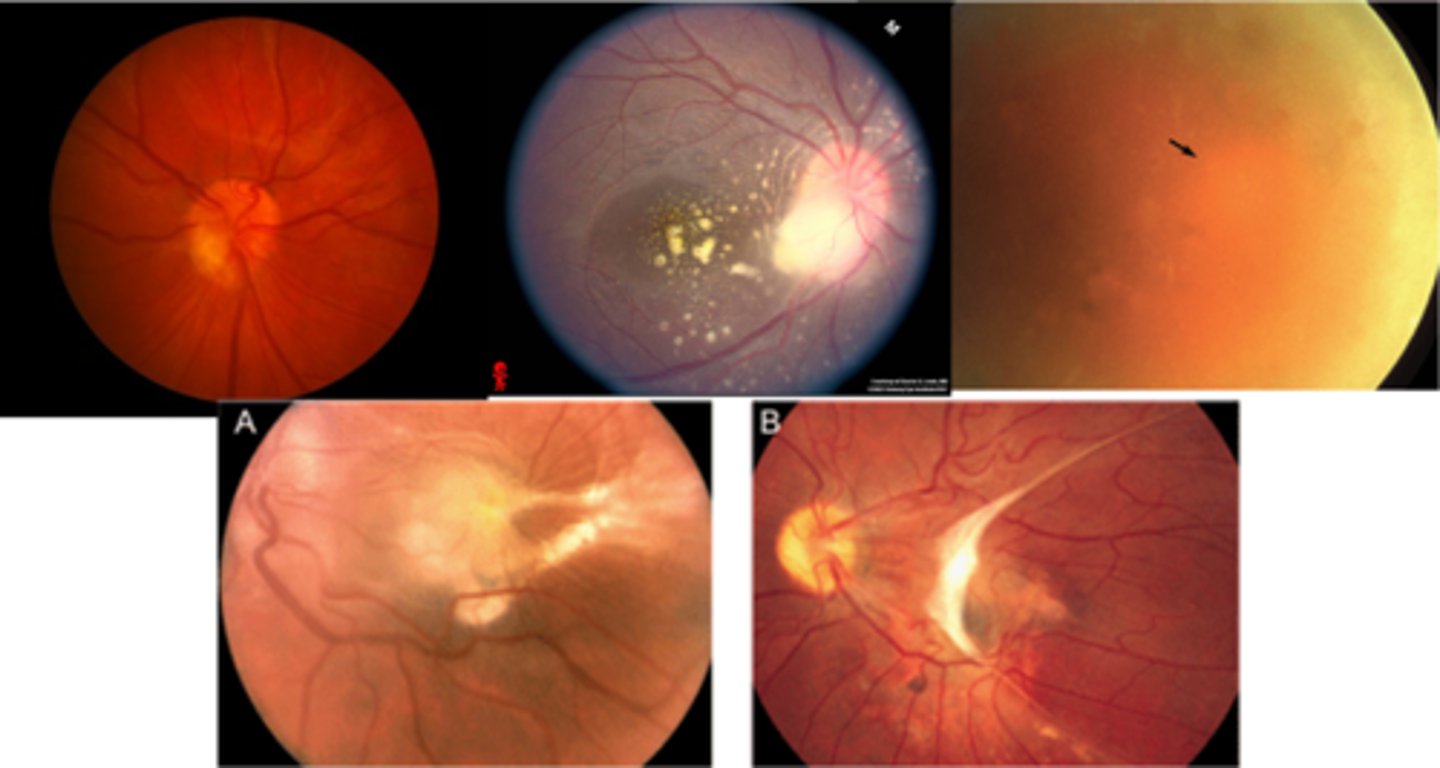

What is ocular histoplasmosis?

multifocal, bilateral chorioretinitis

What causes ocular histoplasmosis?

Histoplasma capsulatum soil fungi or mold = carried by birds or bats, esp seen in the Ohio-Mississippi River Valley = humans inhale spores in poop = affects lungs, other organs

What is the classic triad of signs in ocular histoplasmosis?

"punched-out" chorioretinal scars aka "histo spots" = outer retinal atrophy of ONL, PR's, RPE = scarring = yellow-white sclera or darker RPE hyperplasia

PPA = often further out, more irregular that crescents

absence of vitritis = white translucent dots floating in vitreous

What is ocular toxoplasmosis?

focal, full-thickness retinochoroiditis

What causes ocular toxoplasmosis?

Toxoplasma gondii protozoan parasite = carried by cats (definitive host) but also other humans, mammals, birds, or reptiles (intermediate hosts)

What are the 3 main ocular findings of ocular toxoplasmosis? Differentiate which are active vs latent.

white focal retinitis = active only

overlying vitritis = "headlight in the fog" = active only

nearby large pigmented retinochoroidal scar = active and latent

What finding of toxoplasmosis is seen in A/B?

retinitis turns into hazy scar with nerve pallor

What finding of toxoplasmosis is seen in C/D?

scarring overtime with VA loss/scotoma

What findings of toxoplasmosis are seen here?

retinal vasculitis

exudative scar

focal, hazy vitritis and retinitis

What findings of toxoplasmosis are seen here?

latent scars